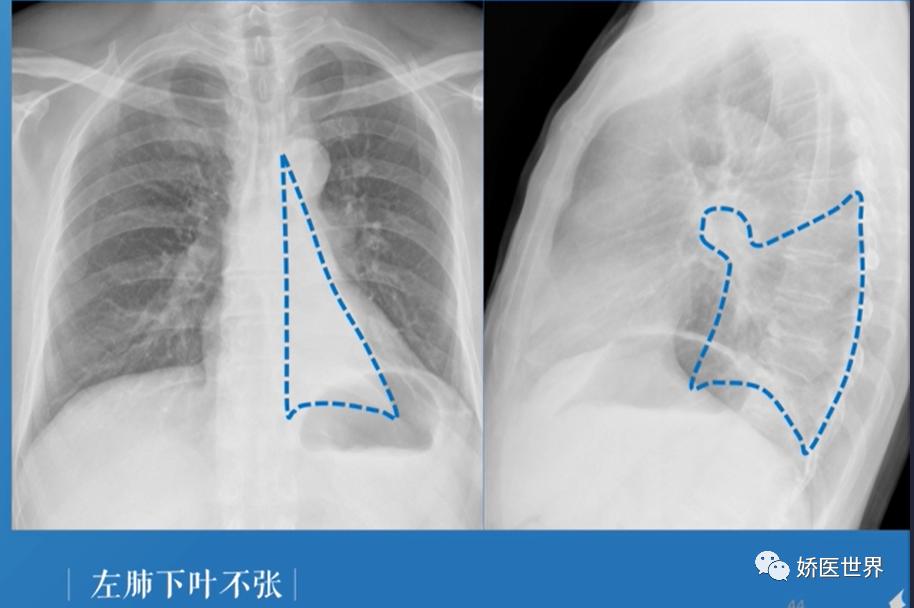

⑤左肺下叶不张